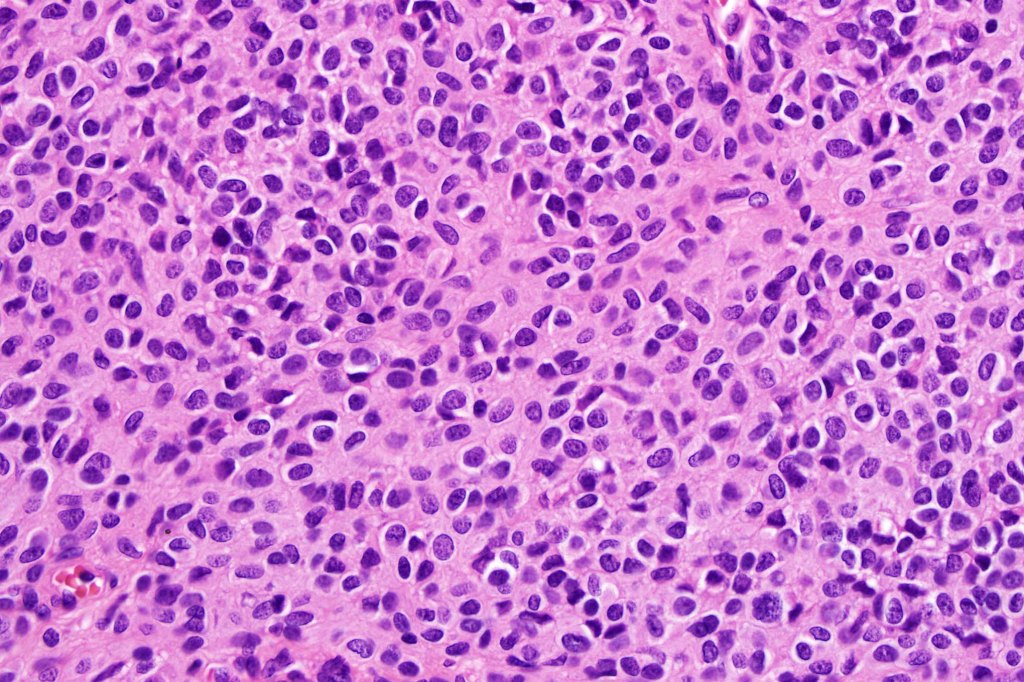

•It is hypercellular and most often composed of epithelioid cells showing little pleomorphism & only occasional mitoses

•Nuleoli are small

•Intracytoplasmic pseudo-inclusions

•The constituent cells are generally larger than the adjacent nevus cells

•Some examples show more marked pleomorphism with prominent nucleoli and increased mitotic activity but abnormal mitoses are not a feature. These are not associated with any sinister biological potential